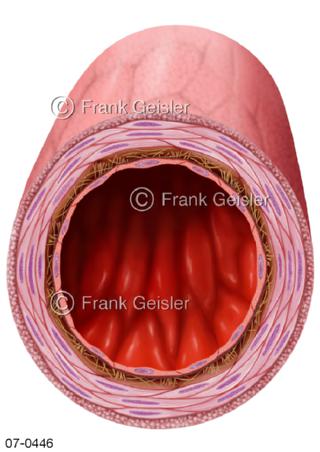

Bilder zu Herz, ein muskuläres Hohlorgan, das den menschlichen Körper durch rhythmische Kontraktionen mit Blut versorgt und dadurch die Durchblutung der Organe sichert, das Kreislaufsystem zeigt den Transport von arteriellem sowie venösem Blut durch das kardiovaskuläre System (Herz-Kreislauf-System), bestehend aus Blutgefäßen, Lymphgefäßen und dem Herz